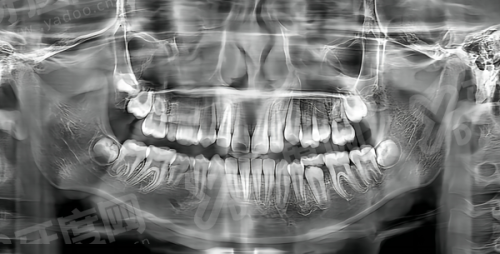

1、呼和浩特万诺口腔医院医生团队经验多,由从业多年口腔骨干医生组成,包括种植医生刘祥宇、王煕等,具备扎实的理论基础和临床技术,擅长复杂病例如全口种植、青少年矫正等。

2、呼和浩特万诺口腔医院团队成员均持有正规执业资质,定期参与专精培训,结合特色护理服务,提供个性化治疗方案,如即刻种植技术缩短疗程,提升患者体验